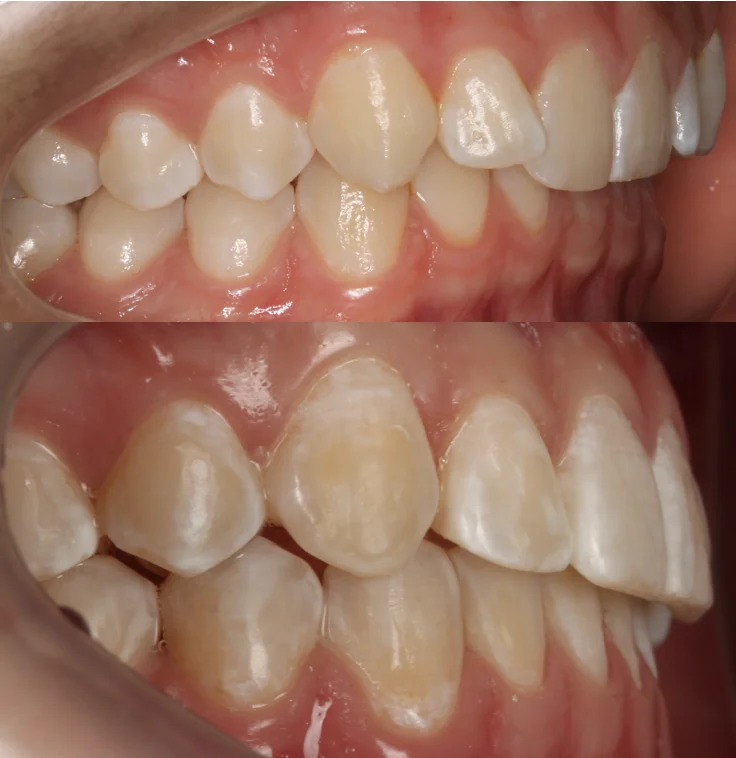

Нарушение соотношения челюстей и неправильное положение зубов — зубные ряды смыкались некорректно, зубы стояли со смещением.

Прозрачные элайнеры Invisalign на обе челюсти. Выровнять зубы и нормализовать смыкание. Срок — около 2 лет.

Лечение заняло 4 года (февраль 2022 — март 2026). Капы менялись каждые 1–2 недели, визиты к ортодонту для контроля и выдачи новых наборов.

Зубы выровнены, смыкание нормализовано. Установлены несъёмные ретейнеры на обе челюсти. Пациент направлен к ортопеду.

Проблема: В клинику обратился мужчина с жалобами на неправильное положение зубов и смыкание — ряды сходились некорректно, зубы стояли со смещением. При этом было важно, чтобы лечение оставалось незаметным для окружающих, поэтому вариант с брекетами не рассматривался.

Решение: Поставили элайнеры Invisalign на обе челюсти. Лечение заняло 4 года — случай потребовал нескольких этапов коррекции, каждый из которых последовательно приближал зубы к нужному положению. Капы менялись каждые 1–2 недели, контрольные визиты — для отслеживания прогресса и выдачи новых наборов. Зубы встали на место, смыкание пришло в норму. Зафиксировали ретейнеры на обе челюсти, пациент направлен к ортопеду для завершающего этапа.